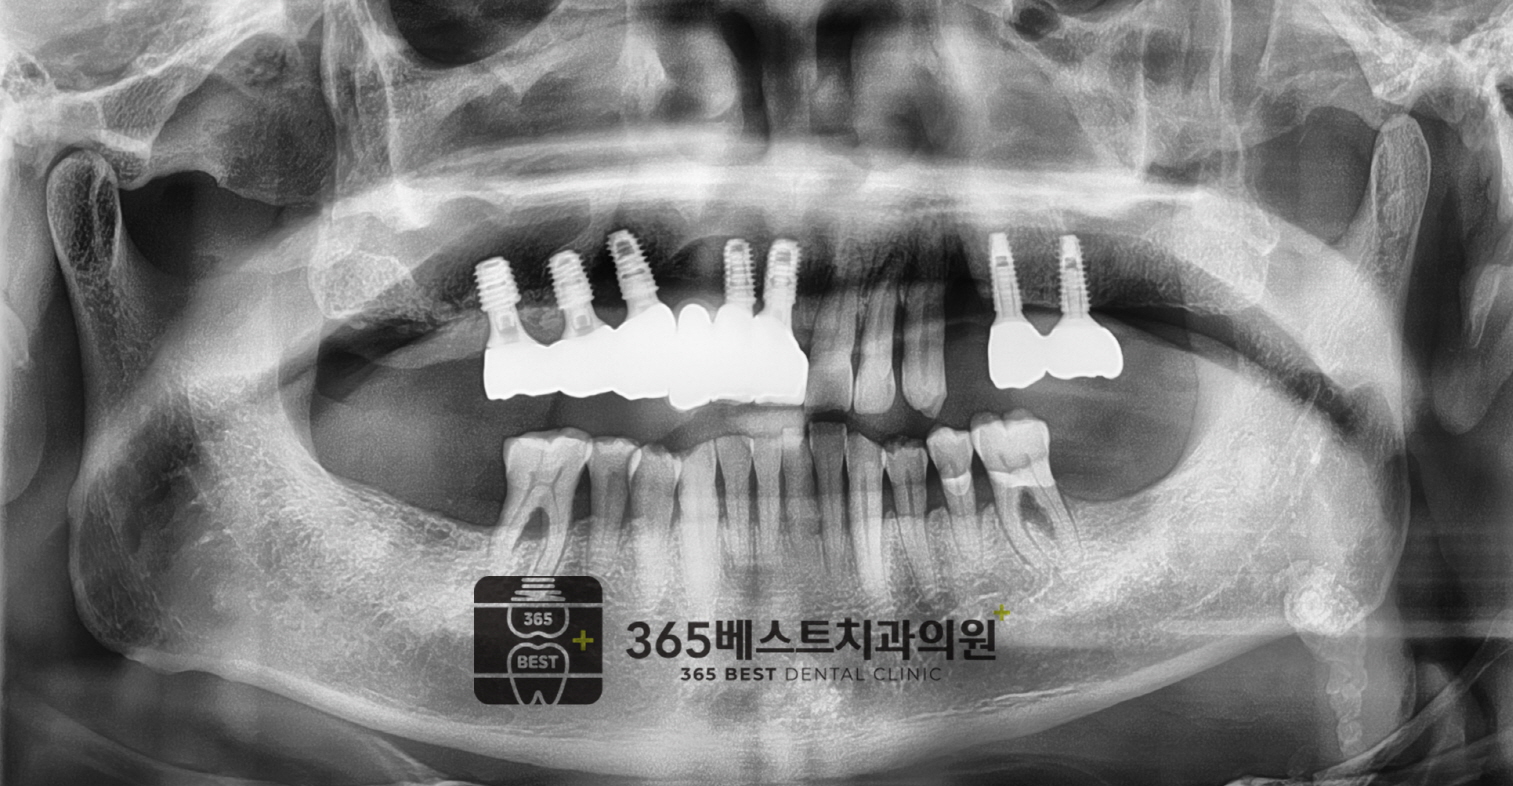

[임플란트]상악동 거상

상악동 거상/66세 남성

(전)